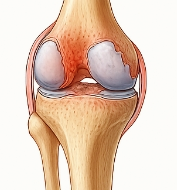

관절염에 좋은 음식 관절염이란?

관절염은 관절 부위에 염증이 생겨 통증, 뻣뻣함, 운동 제한을 유발하는 질환입니다. 특히 퇴행성 관절염(골관절염)과 류마티스 관절염이 대표적인 유형입니다. 다양한 원인으로 관절이 손상되면서 증상이 나타나며, 관절염에 좋은 음식을 통한 관리가 중요한 이유도 여기에 있습니다.